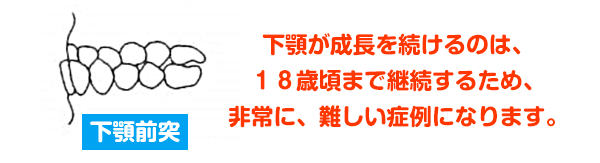

12歳以降は、下顎の前方への発育が、盛んになります。(受け口になる可能性が高くなり、受け口になるのはこの時期です。)

上顎骨の前方への発育抑制と、下顎が、自由に動かす事の出来ない状況にあると思われます。

また、遺伝性の下顎骨反対咬合の傾向があり、将来、大学での手術になるリスクがあります。